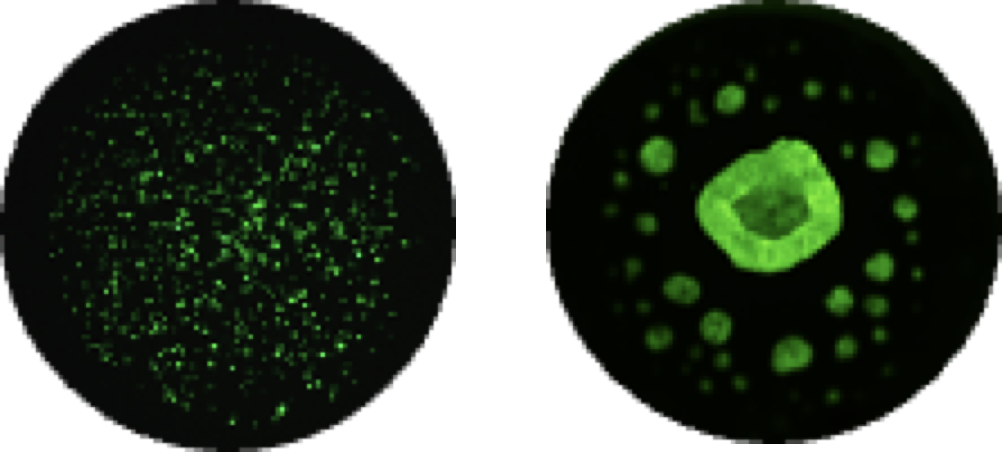

튜머로이드 배양 기반 암환자 치료 반응을 예측하는 서비스로 인체에서 유래한 암조직을 실험실에서 배양하여

환자가 투여하고자 하는 항암제와 반응시켜 어떠한 항암제가 적합한지 알아보는 검사입니다.

1) 검체 채취 및 전처리

2) Pillar Plate 위에 검체를 분주

3) 3D 튜머로이드 배양

4) 약물 반응성 검사

5) 결과 관찰 및 분석

결과분석은 Multiparameter based index (MPI, CODRP®)에 의해 이루어지며 이에 해당되는 요소로는 1) AUC curve, 2) Tumoroid의 성장률(growth rate), 3) Tumor의 stage입니다.